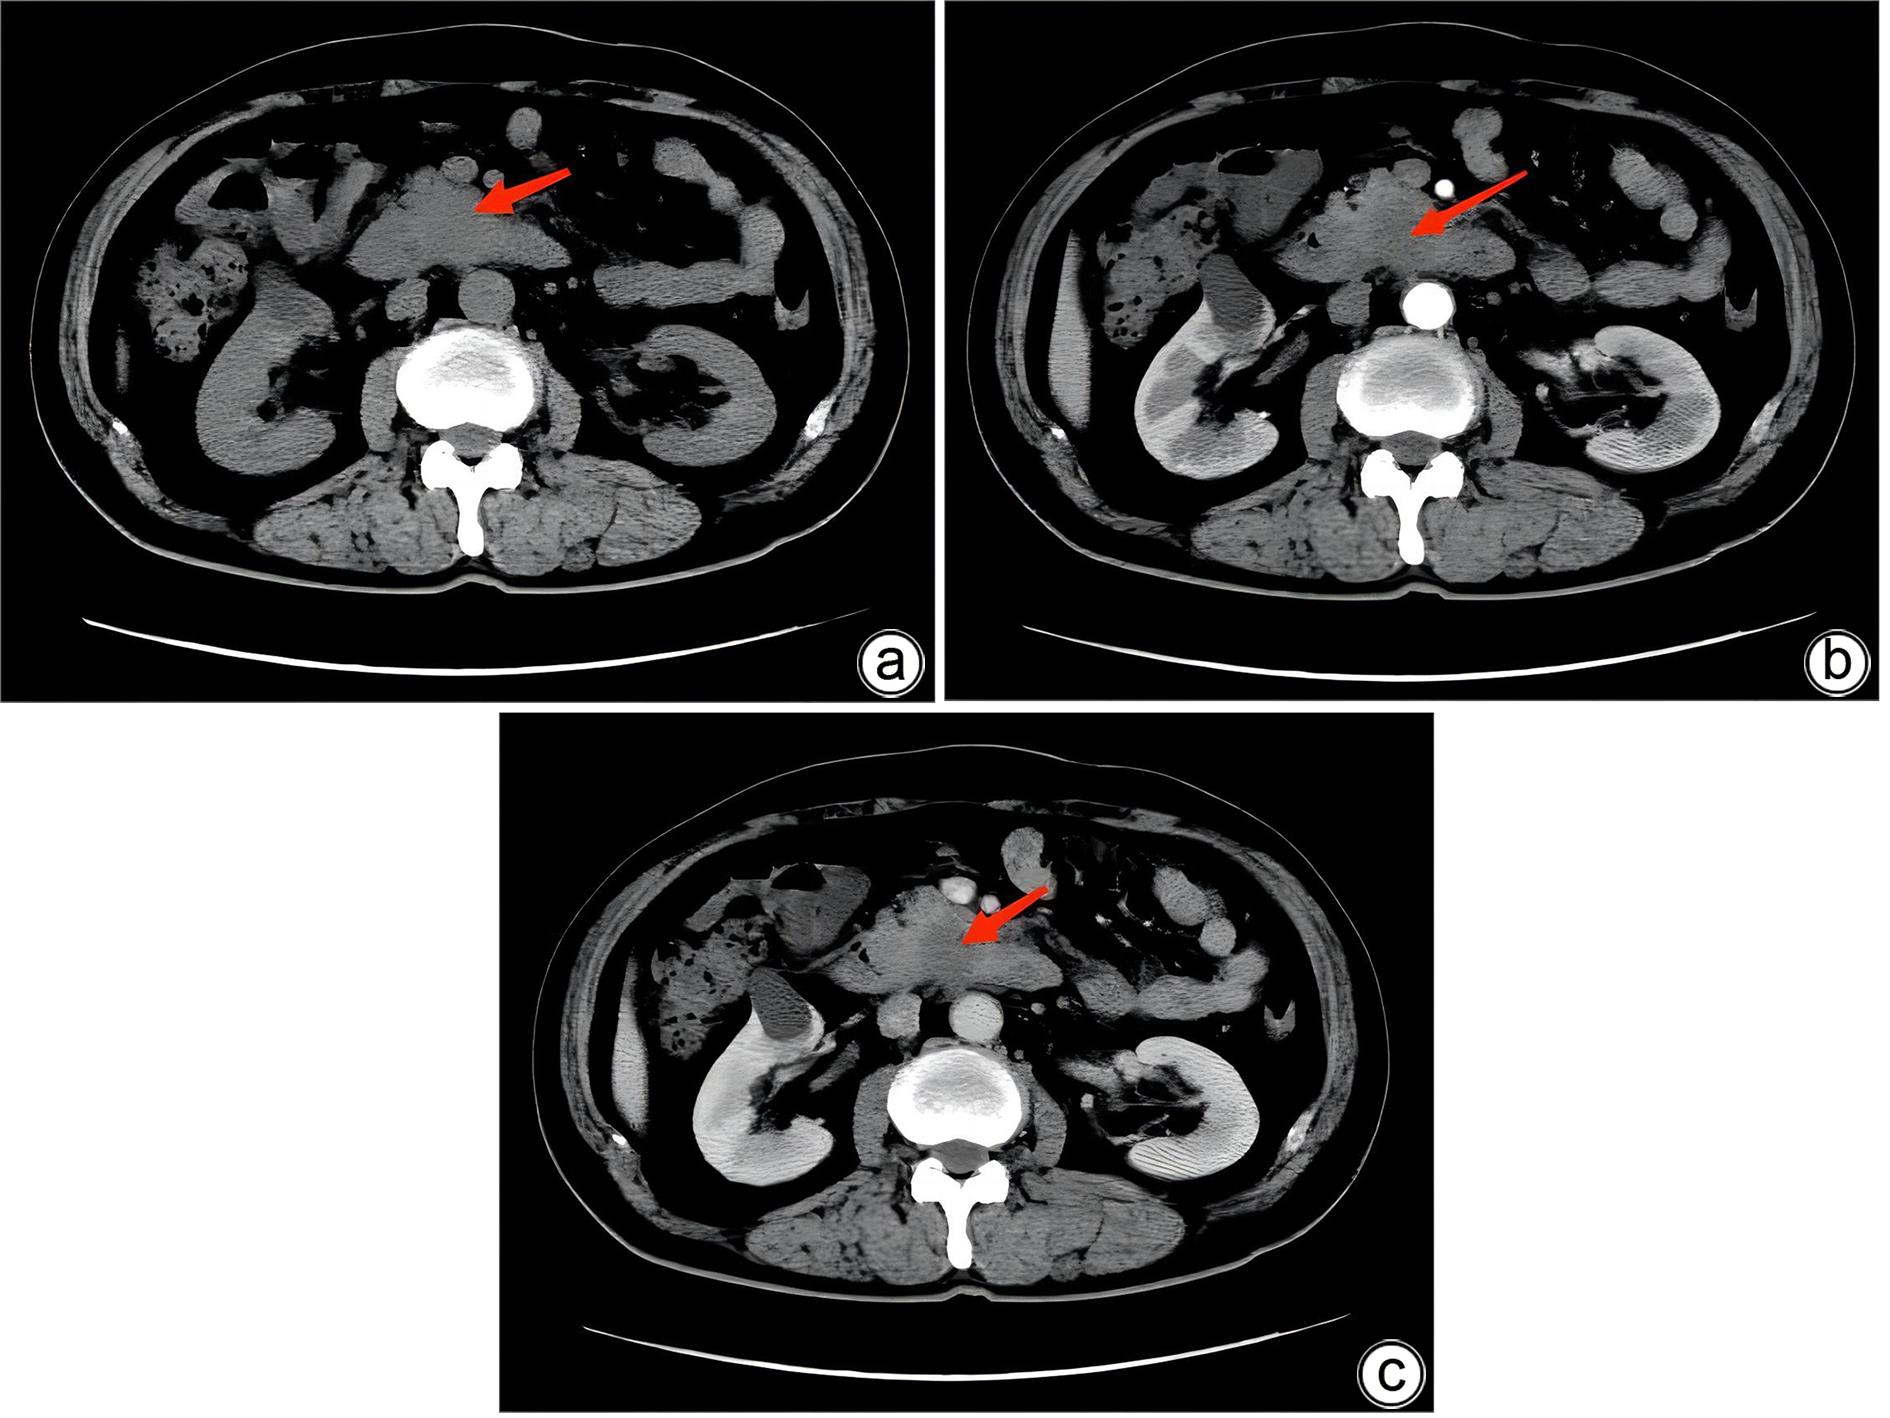

胰腺内副脾误诊2例报告

2024, 40(2): 365-368. DOI: 10.12449/JCH240223

摘要(1364) HTML (331) PDF (1188KB)(158)

摘要:

副脾是指正常脾脏以外存在的,与主脾结构相似,有一定功能的脾脏组织,其中完全被胰腺包裹的胰腺内副脾(IPAS)发生率仅为2%,因其临床症状不典型,影像学特征与胰腺神经内分泌肿瘤、胰腺实性假乳头状瘤以及其他胰腺占位性病变较为相似,临床上容易误诊。本文报道了2例分别被误诊为胰腺神经内分泌肿瘤和胰腺实性假乳头状瘤的IPAS患者,并分析误诊原因,总结诊疗经验,以期提升临床对IPAS明确鉴别诊断的认识。